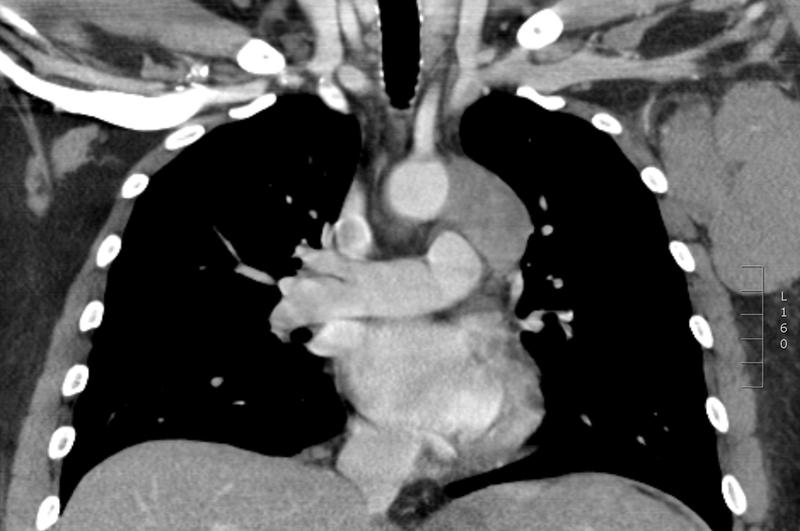

Gallery Mediastinum Lymphoma Lymphoma -Mediastinal and left axillary nodes

Lymphoma -Mediastinal and left axillary nodes